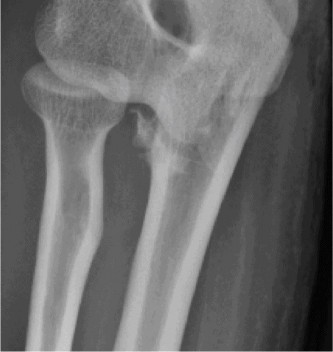

A 22-year-old male with a history of multiple shoulder dislocations was treated with an arthroscopic Bankart repair 9 months ago. Over the last 3 months, he has tried returning to sports but reports continued anterior subluxation events. Revision surgery has been recommended, and he comes to you for a second opinion. His CT

scan is shown above (Fig. 2–36).

Figure 2–36

What is the most appropriate treatment option?

The correct answer is (B). In patients who have undergone a capsulolabral repair for instability and continue to be symptomatic, it is important to carefully assess the degree of glenoid bone loss. This is best done with a 3D CT scan. When viewing sagittal images, the inferior two-thirds of the glenoid should be a perfect circle. Bony defects can be appreciated by loss of this circle with bone missing from the 230 to 430 position. This may result in the glenoid taking on the classic inverted pear-shaped configuration that is associated with recurrent anterior instability (see Fig. 2–37). The average circle diameter is 24 mm and the average bone loss associated with a pear-shaped glenoid is 35% or 7.5 mm off the anterior rim. The critical amount of bone loss that destabilizes the shoulder is between 15% and 25% hence bone loss at or above this level must be treated with a bony procedure rather than capsulolabral repair.

Figure 2–37_Sagittal depiction of the glenoid. Bone loss of 8 mm in the AP direction corresponds to approximately 35% and will likely require bony reconstruction. (Reproduced with permission from Piasecki DP, Verma NN, Romeo AA, et al. Glenoid Bone Deficiency in Recurrent Anterior Shoulder Instability: Diagnosis and Management. _JAAOS 2009;17(8):482–493.)

Answer A is incorrect as additional PT after a year is not going to make a difference especially given the degree of bone loss. Answer C is incorrect as no fixable bony fragment is seen. Answer D is incorrect as no significant Hill–Sachs lesion is seen on imaging; however, a Hill-Sachs lesion, if present, would contribute to ongoing instability. A Boyd–Sisk (Answer E) procedure was historically described for anterior instability but is no longer used. Objectives: Did you learn...? The physical examination findings associated with anterior instability?